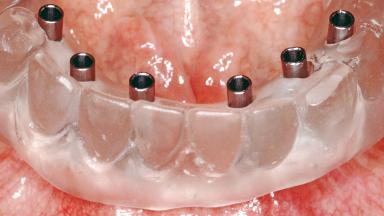

Conventional Loading of Six Implants in the Mandible and Final Restoration with a Full-Arch Metal-Ceramic FDP

A 68-year-old, completely edentulous male patient presented for evaluation and treatment options. He reported excellent general health and was taking no regular medication. He had been edentulous for approximately 12 years, having lost his teeth to periodontal disease and dental caries. The patient’s chief complaint was incompetent function. His secondary concerns included his appearance and the desire for a predictable outcome. He attributed his reduced functional capacity to his lower complete denture, which he described as poor. He was particularly concerned with the denture’s instability and poor fit. In general terms, he was satisfied with the maxillary complete prosthesis. The maxillary prosthesis was characterized by adequate retention, stability, and support, although the fit was considered less than ideal.

# of Implants 6

Type of Implants One-Piece

Prosthesis Type FDP

Retention Screw-retained, with 4 or more splinted implants Screw-retained, with 4 or more splinted implants